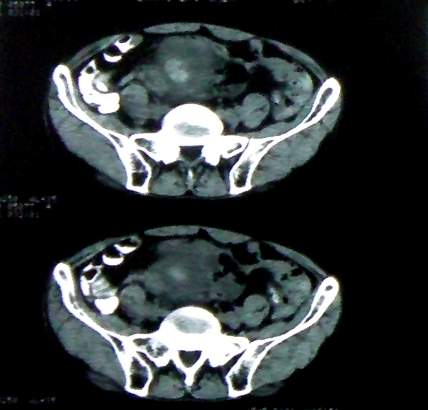

男 60岁,下腹部肿块半年余

前列腺肥大,密度不均。伴盆腔实性肿块。考虑前列腺癌伴盆腔转移。建议增强扫描。

考虑来源于肠道的肿瘤,乙状结肠?询问排便情况

乙状结肠间质瘤

病理结果:肠系膜肉瘤

病灶形态不规则,偏心性裂隙样坏死,支持恶性病变。来源不好定。感谢反馈结果--肠系膜肉瘤。